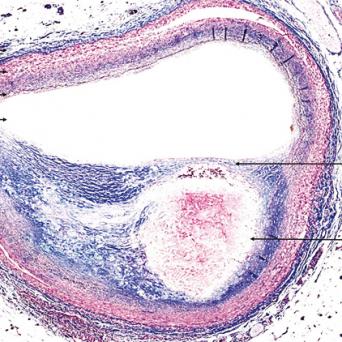

Microangiopathie thrombotique

La microangiopathie thrombotique (MAT) est une urgence médicale. Elle recouvre plusieurs pathologies aux mécanismes, tableaux cliniques et traitements distincts. Les progrès récents dans la compréhension de leur physiopathologie ont permis de mieux les identifier et les classifier, tandis que des thérapeutiques spécifiques en ont grandement amélioré le pronostic. Une identification précoce est donc cruciale.